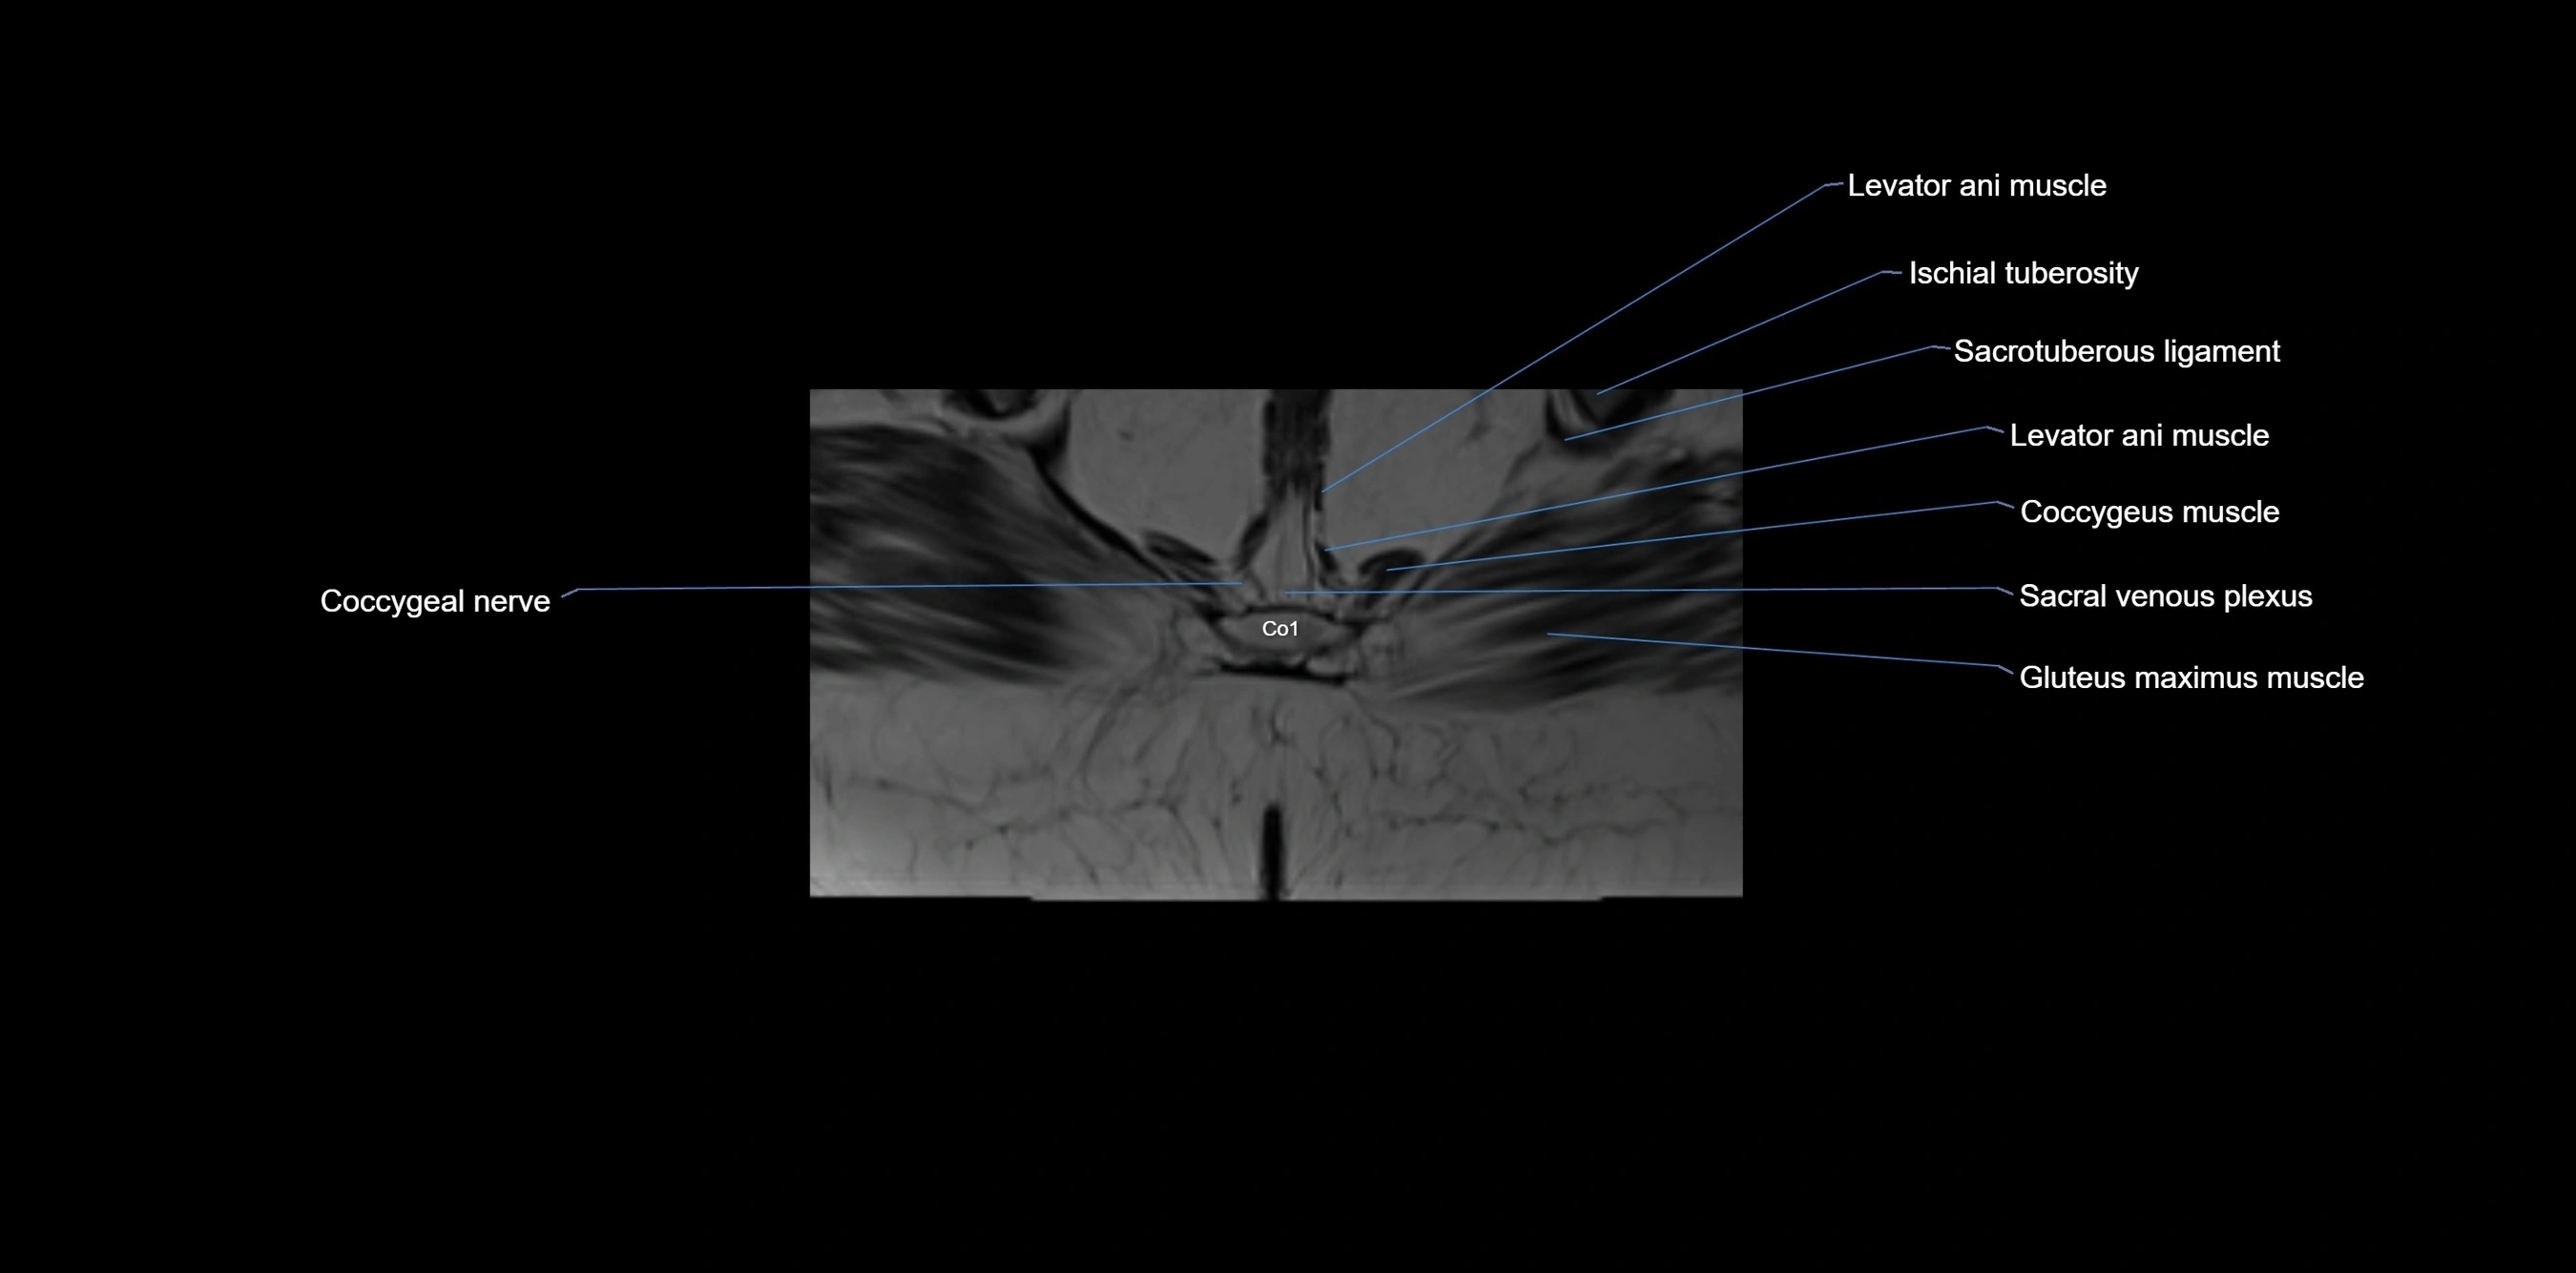

MRI image

image